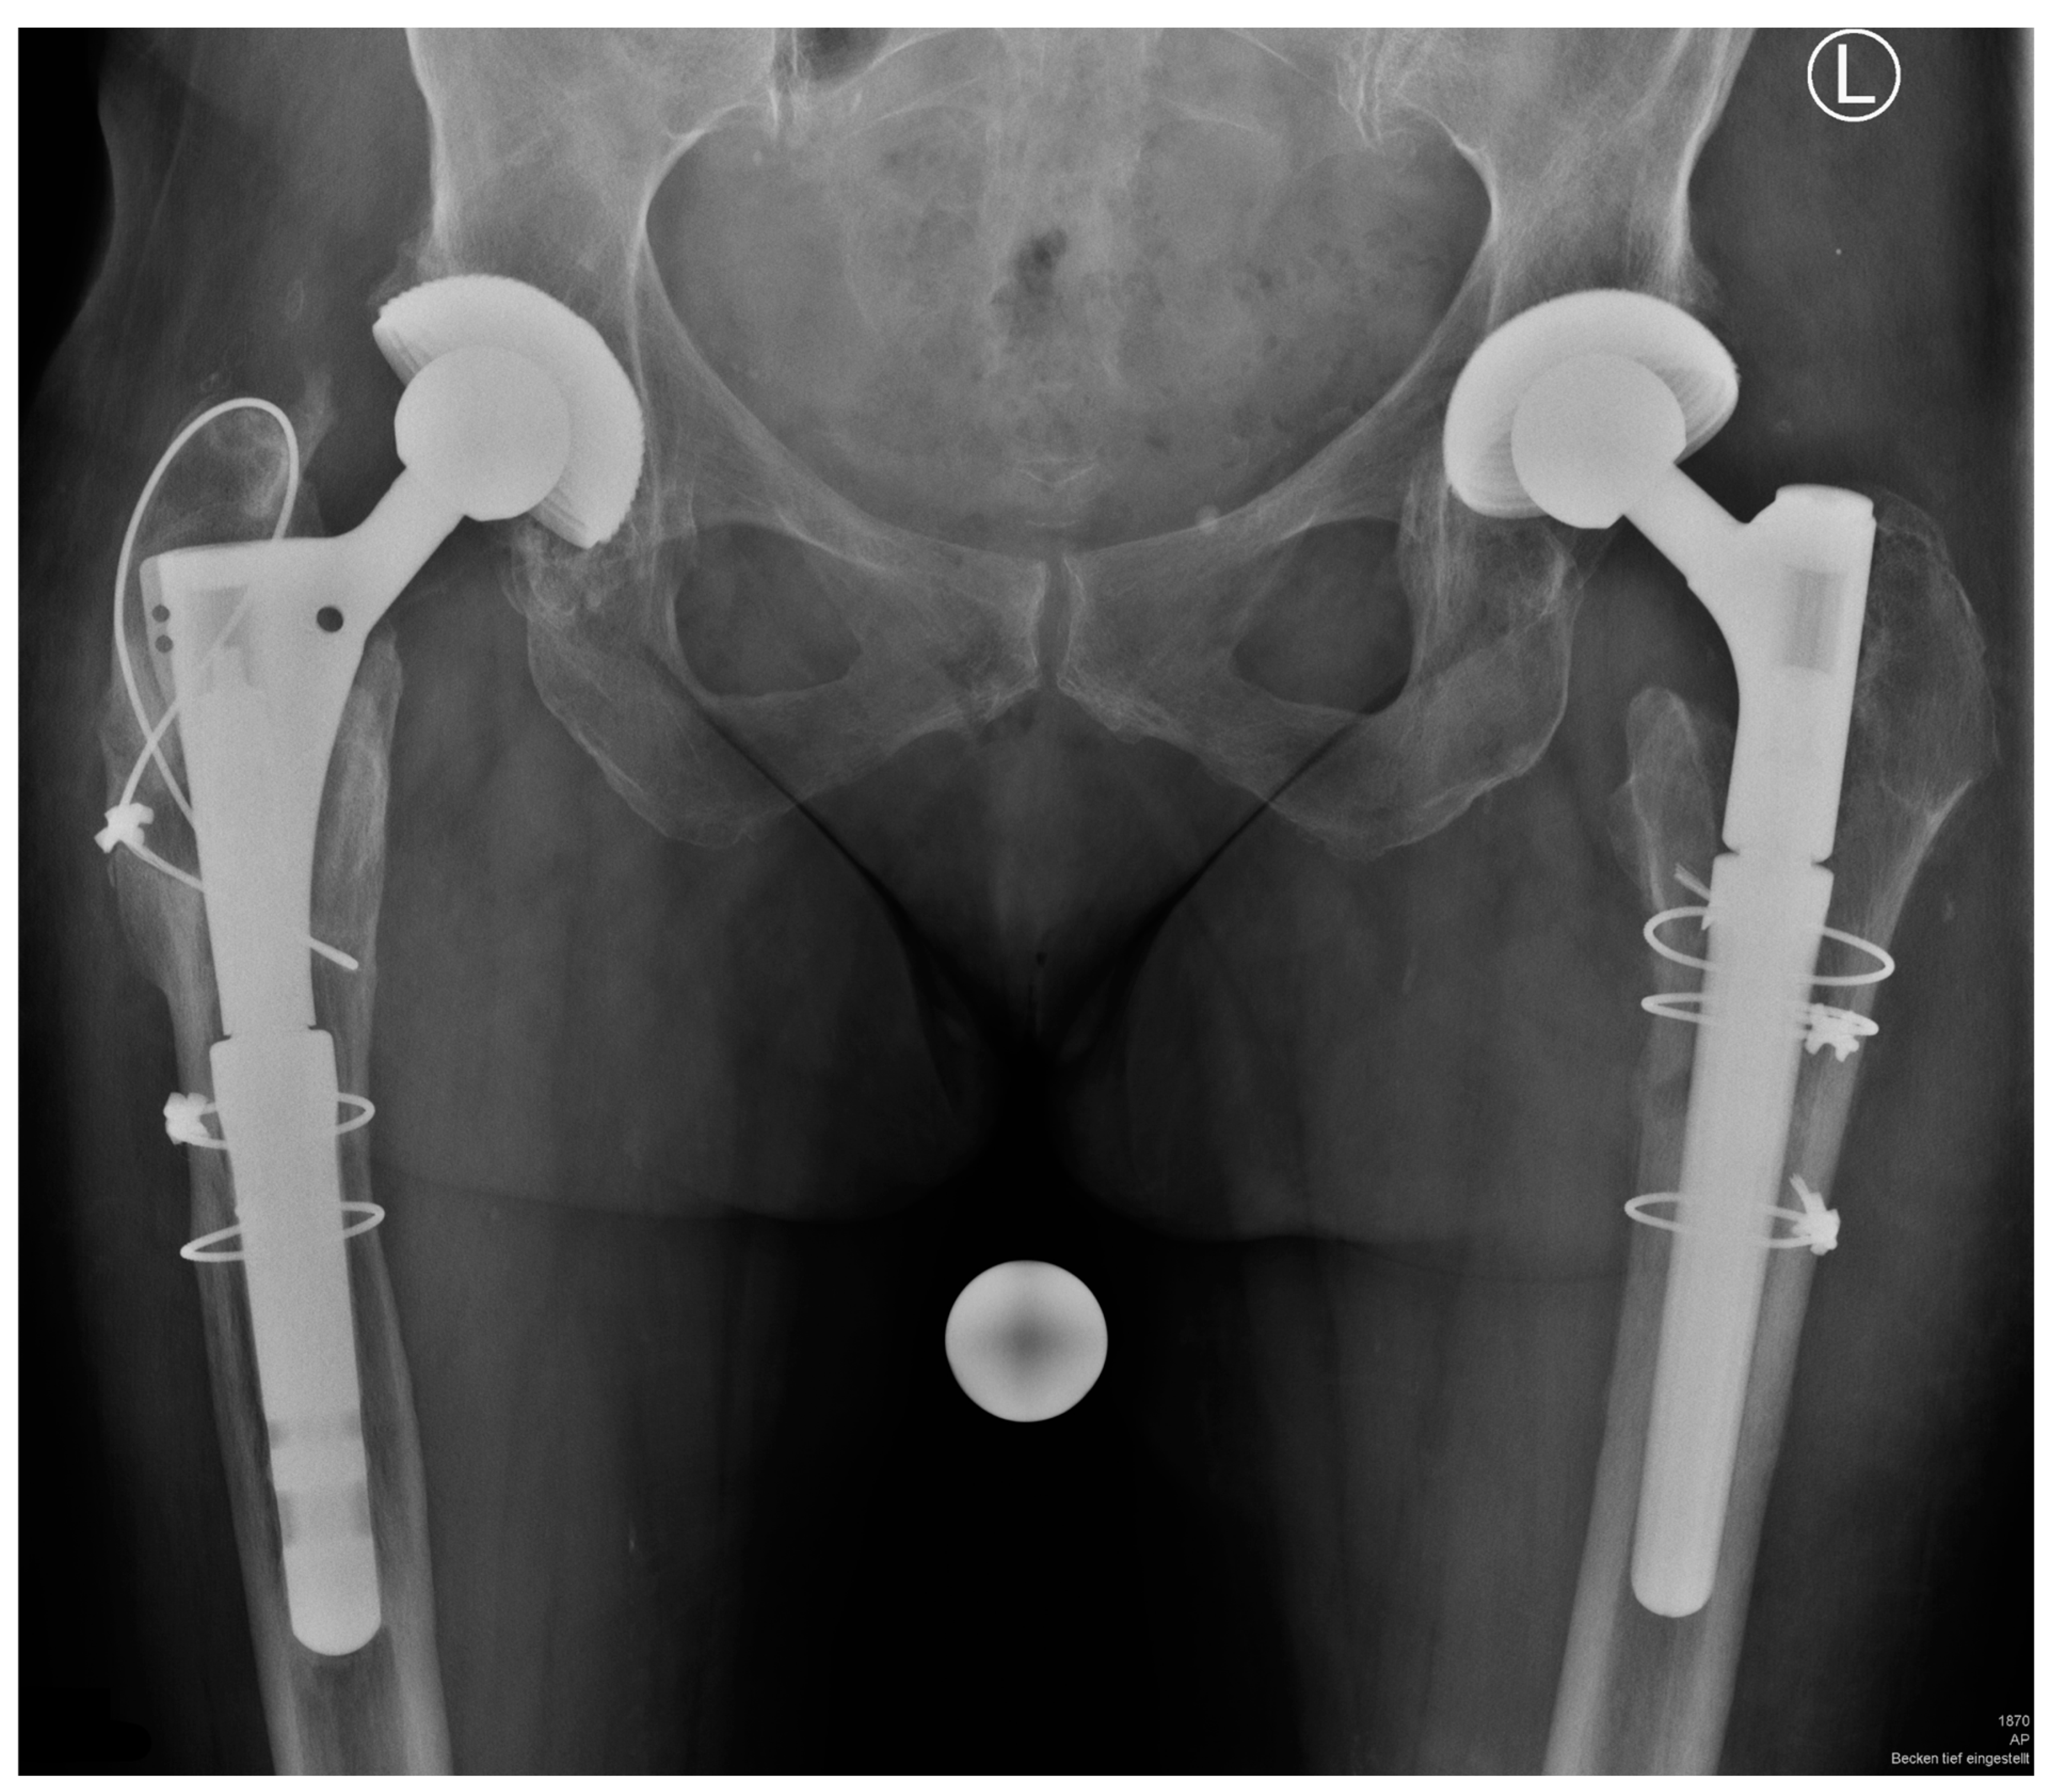

| Patients Sex, Age (Year) | Indication # | Stem Configuration * | BMI | Bone Defect | Breakage Po. (Year) |

|---|---|---|---|---|---|

| m., 82 | ppf | c, 21, 200, lat, long, m | 27 | 3A | 2.8 |

| f., 55 | al | s, 16, 140, lat, short, s | 33 | 2 | 5.4 |

| m., 58 § | al | s, 30, 200, lat, short, s | 44 | 3A | 3.5 |

| m., 47 | ts | c, 16, 200, lat, short, s | 45 | 2 | 5.5 |